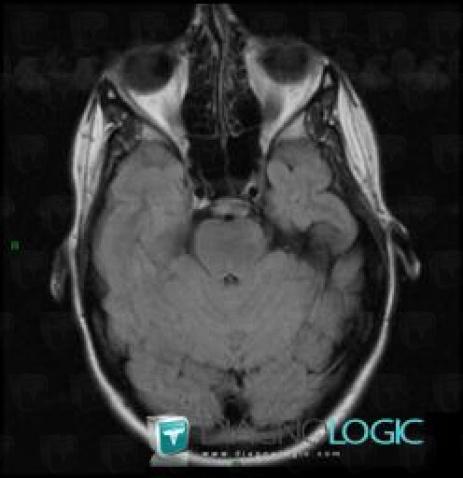

Télangiectasie capillaire, Fosse postérieure, IRM

Voici les informations spécifiques à l'image clé ci dessus:

- Diagnostic Télangiectasie capillaire, Localisation(s) Fosse postérieure, comportant les gammes Lésion infratentorielle en isosignal T2 ou FLAIR